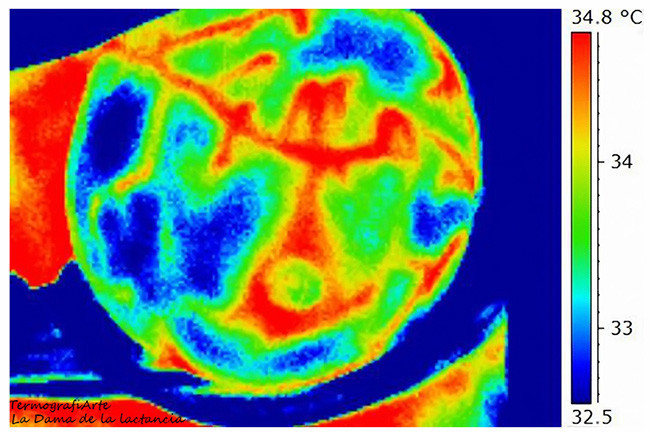

Una es la que veis arriba, que su autor, Jorge Martin, quiso titular "La Dama de la Lactancia", por la imagen que se forma, similar a la de un espadachín en pleno duelo. Lo más curioso de la imagen, que no pudimos apreciar en la otra porque no disponíamos de la leyenda, es poder ver en grados centígrados las variaciones que se producen.